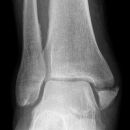

distaler Unterschenkelschaft

Spiralfraktur Tibia